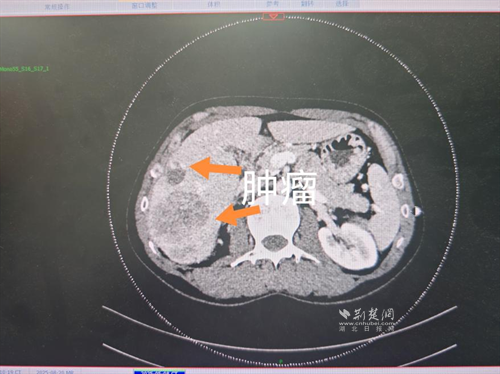

經(jīng)過(guò)肝膽外科牽頭組織的多學(xué)科MDT會(huì)診,團(tuán)隊(duì)確認(rèn)其適合接受當(dāng)前國(guó)際先進(jìn)的釔90樹脂微球選擇性內(nèi)放射治療。治療僅一個(gè)月后,患者病灶即從10cm縮小至6cm;術(shù)后六個(gè)月復(fù)查顯示,病灶體積進(jìn)一步縮小近40%,影像學(xué)檢查提示完全緩解,臨床分期成功轉(zhuǎn)化,達(dá)到手術(shù)切除標(biāo)準(zhǔn)。